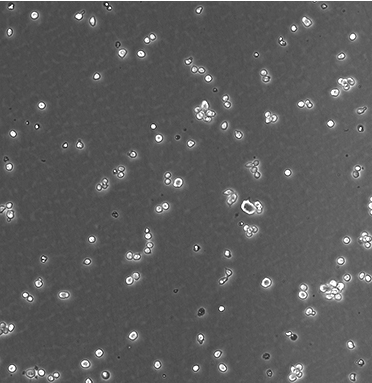

NAMALWA

產品名稱 NAMALWA

中文名稱 人Burkitt's淋巴瘤細胞

組織來源 Burkitt's淋巴瘤;女性

生長特性 suspension

形態(tài)特征 lymphoblast

傳代方法 Resuspending the cells in fresh medium at 5×10^5 viable cells/mL and subcultured at 2×10^6 cells/mL.

細胞描述 The cells contain the Epstein-Barr virus(EBV) genome.